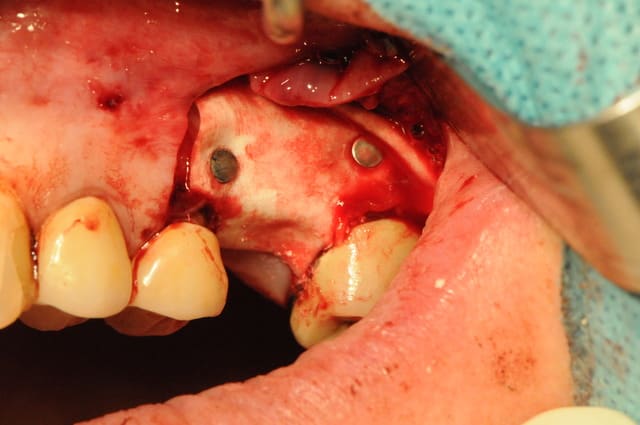

Le deuxième dépucelage concerne mon premier SINUS LIFT.

Hormis le fait que mon insert mectron se soit cassé pendant l'intervention, tous le reste s'est plutôt bien passé.

J'ai terminé avec la boule diamantée.

* le volet osseux est trop bas donc la corticale est épaisse et le décollement plus compliqué.

- position de la fenêtre latérale : il est pratique de mesurer sur l'OPG ou le scanner la hauteur de crête et de reporter cette mesure in situ, cela t'éviteras de taper dans la corticale et d'avoir un accès décalé et plus génant. Dans le cas où la hauteur de crête est très fine 2-3 mm, il est dans tous les cas fortement conseillé de rester à un minimum de 5mm de cette dite crête et ce afin d'éviter un effondrement crestal difficile à régénerer.

- taille de la fenêtre latérale : elle est dans ton cas acceptable même si j'ai l'habitude d'ouvrir un peu plus ... accès et élévation en sont facilités.

- volet osseux : de par ta préparation à la fraise boule il t'était impossible de repositionner le volet osseux en fin de chirugie. La logique voudrait que tu repousses ce volet dans le sinus afin de créer un "pseudo plafond sinusien". A la vue de tes photos il semblerait que tu es tout de même enlevé ce volet. Est ce que je me trompe ? si oui oublies ma question, si non pourquoi ?

- fracture d'insert mectron : quel est la référence de l'insert qui s'est cassé. Sous quel programme s'est il cassé? J'utilise le mectron pratiquement tous les jours. J'ai en 4 ans d'utilisation cassé un seul insert et par ma faute puisque j'ai alors utilisé un programme inadapté à l'insert.

- implantation simultanée : comme amibien le décrit j'aurais également dans ton cas opté pour une mise en place implantaire dans la foulée puisqu'il n'y a aucun doute à la vue de ton OPG qu'une stabilité primaire aurait été obtenue sans problème avec un implant conique.

- membrane de recouvrement : comme je l'ai écrit dans une autre post, plusieurs review de qualité s'accordent à dire que la recouvrement de la fenêtre d'accés est en corrélation avec un taux de survie implantaire amélioré à long terme. Je n'ai donc rien à te reprocher à ce niveua là. Cependant, j'aurais dans ton cas deplacé mon incision de décharge en mésial de la 25 afin d'éviter d'avoir ma limite membranaire en dessous de mon trait d'incision. Cela évite des complications d'éventuelle exposition si un point lache.